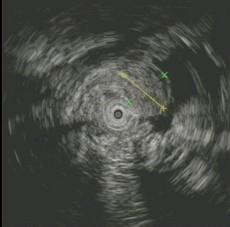

问题 患者,女性,30岁,上腹不适2周,查体:心肺腹未见异常。电子胃镜图片如下,病变部免疫组化CD117阳性,SMA阴性,VIM阳性,诊断为 ( )

选项 A.胃底息肉 B.胃体息肉 C.胃底平滑肌瘤 D.胃体平滑肌瘤 E.胃底间质瘤

答案 E